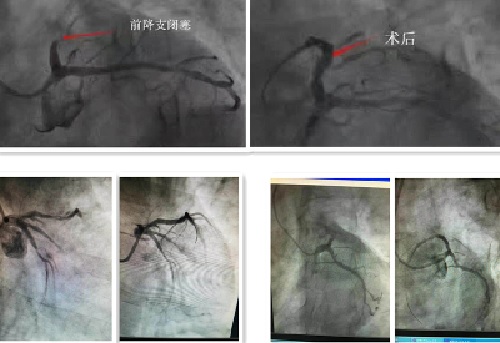

面对突如其来的考验,我院医护人员保持着异常清醒的头脑和娴熟的手法,麻醉、穿刺、建立通道、造影、球囊扩张、植入支架……手术进展迅速而有条不紊。随后,手术室喜讯频传,三名患者相继脱离了生命危险,起死回生。从患者入院到血管开通,时间均在60分钟内,又一次刷新了抢救记录。此刻,时针已经指向了凌晨一点,汗水浸透了医护人员的衣衫。对于许多人来说,这是一个普通的夜晚。而这一夜,我院的医护人员们用精湛的医术诠释了白衣天使的使命与担当,书写生命的奇迹。